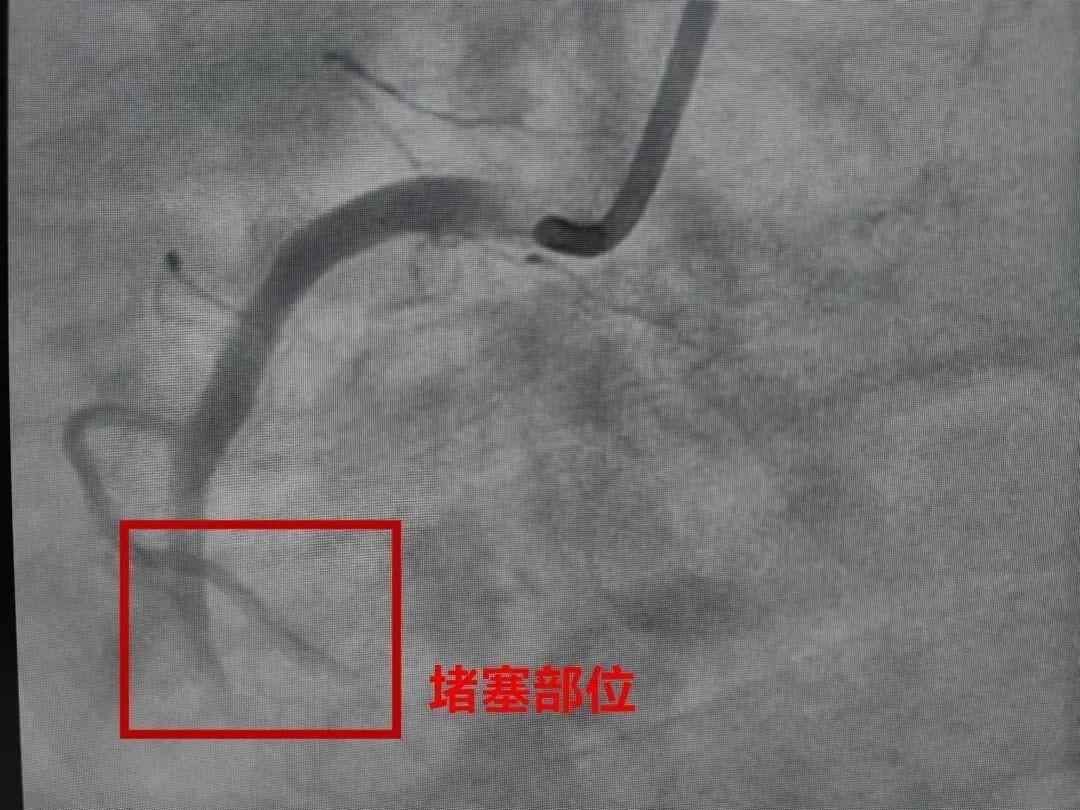

今年7月,41岁的韩先生在江苏出差时与朋友猛喝了几杯冰啤酒后突发胸痛,随即意识丧失被送医。经诊断,其右冠状动脉近段完全闭塞,经紧急手术抢救才脱险。

它是由于冠状动脉发生堵塞

出现急性、持续性的缺血缺氧

从而引起的心肌坏死